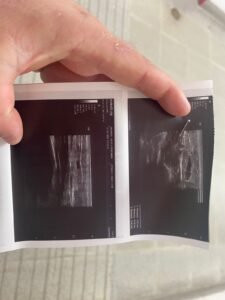

Fui atendido en el servicio de Traumatología del Hospital Julio C. Perrando, donde, tras estudios como ecografía de partes blandas y análisis de sangre, se indicó una intervención quirúrgica de toilette para drenar el absceso y tratar la infección. El procedimiento implicó un cierre por segunda intención, permitiendo la cicatrización de adentro hacia afuera.

Adjunto las pruebas que respaldan el comunicado.